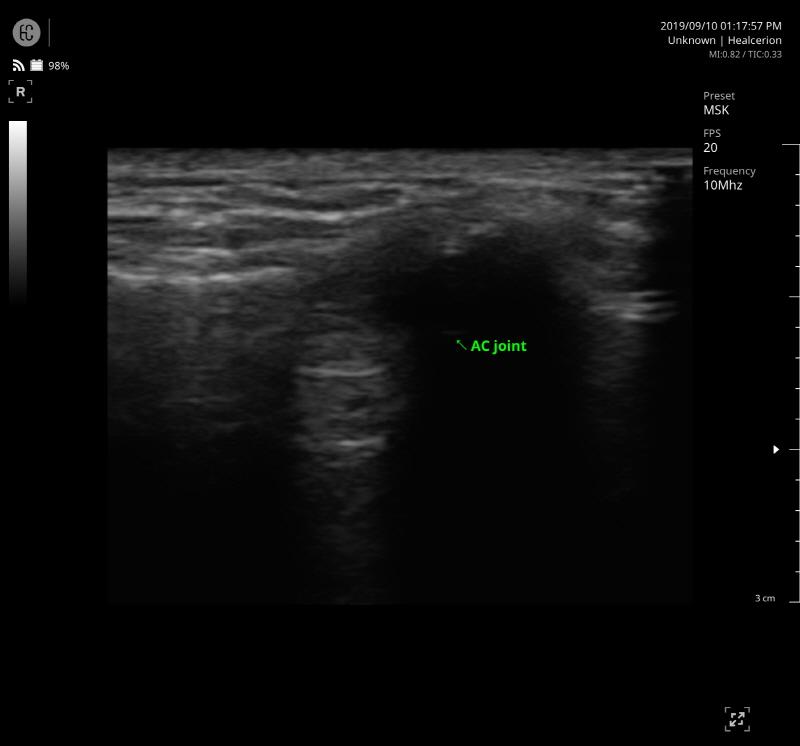

SONON 300L ecografía 1 SONON 300L ecografía 2 SONON 300L ecografía 3